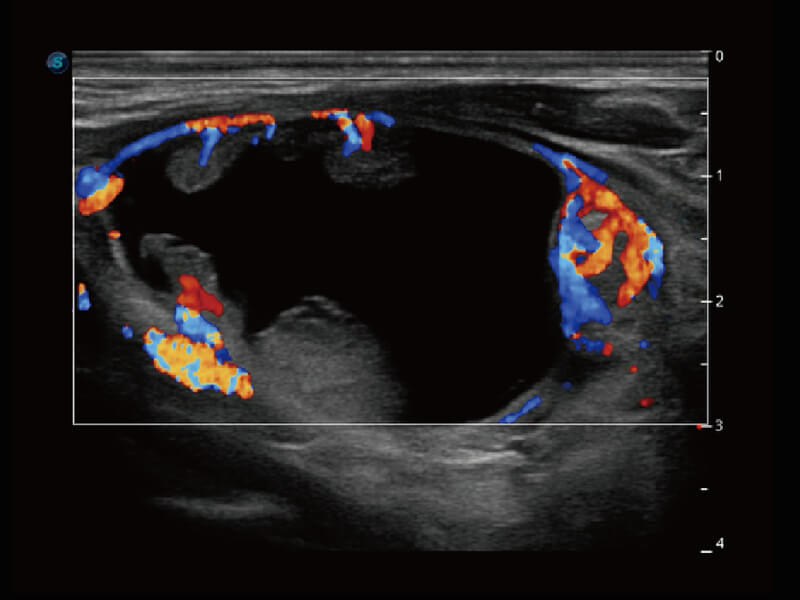

彩色多普勒超声诊断系统